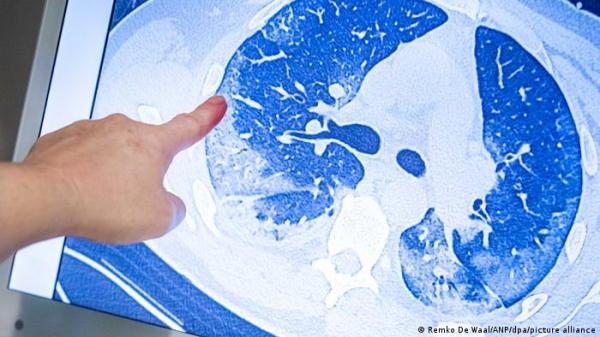

خلص باحثون بريطانيون إلى أن متحور أوميكرون ربما يكون أقل فعالية في مهاجمة الرئتين مقارنة بالمتحورات الأخرى لفيروس كورونا. وذكرت وكالة بي ايه ميديا البريطانية أن دراسة معهد كامبريدج لعلم المناعة العلاجي والأمراض المعدية توصلت إلى أن المتحورات في بروتين سبايك، التي تجعلها قادرة على تجنب الأجسام المضادة، ربما تحد أيضاً من كيفية تكاثره في الرئتين وبالتالي تسببه في حدوث أعراض حادة.

وكتب تغريدة قال فيها: "ماذا يعني كل ذلك؟ العدوى في خلايا الرئة يمكن أن ترتبط بحدة المرض الذي يصيب الرئة. وغالباً يمكن رصد خلايا مندمجة في الأنسجة التنفسية التي يتم اختبارها عقب الإصابة بمرض حاد. متحور دلتا كان يمكنه فعل الأمرين، على عكس متحور أوميكرون. مازال يتعين القيام بمزيد من الدراسات".